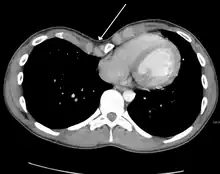

Many scales have been developed to determine the degree of deformity in the chest wall. Most of these are variants on the distance between the sternum and the spine. One such index is the Backer ratio which grades severity of deformity based on the ratio between the diameter of the vertebral body nearest to xiphosternal junction and the distance between the xiphosternal junction and the nearest vertebral body.[17] More recently the Haller index has been used based on CT scan measurements. An index over 3.25 is often defined as severe.[18] The Haller index is the ratio between the horizontal distance of the inside of the ribcage and the shortest distance between the vertebrae and sternum.[19]

Pectus excavatum requires no corrective procedures in mild cases.[22] Treatment of severe cases can involve either invasive or non-invasive techniques or a combination of both. Before an operation proceeds several tests are usually performed. These include, but are not limited to, a CT scan, pulmonary function tests, and cardiology exams (such as auscultation and ECGs).[23] After a CT scan is taken, the Haller index is measured. The patient's Haller is calculated by obtaining the ratio of the transverse diameter (the horizontal distance of the inside of the ribcage) and the anteroposterior diameter (the shortest distance between the vertebrae and sternum).[24] A Haller Index of greater than 3.25 is generally considered severe, while normal chest has an index of 2.5.[19][25][26] The cardiopulmonary tests are used to determine the lung capacity and to check for heart murmurs.[27]